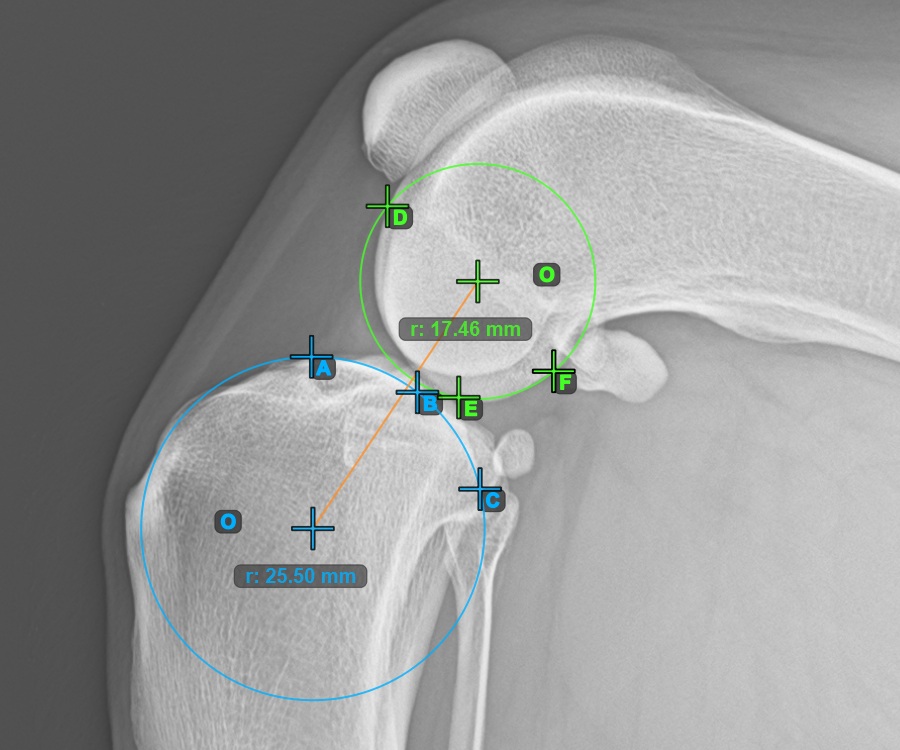

To complete the TTA - 1 Condylus variant of TTA measurement procedure mark the most dorsal point of the Crista Tibiae (Tuberositas Tibiae). The distance between the Tuberositas Tibiae and the line passing along the most cranial point of the Patella is the required adjustment for the TTA procedure.

The image below depicts the usual placement of the tibial tuberosity, the most prominent point of the tibial crest.

Modify the points constructing the measurement to recalculate the required advancement that should be made during the TTA procedure.